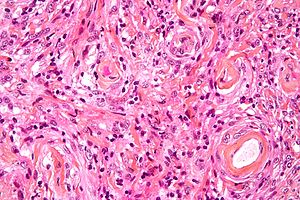

|

Meningioma. HPS stain. | |

Microscopic

Features (memory device WCN):

- Whorled appearance - key feature.

- Calcification, psammomatous (target-like appearance; (tight) onion skin).

- +/-Nuclear pseudoinclusions - focal nuclear clearing with a sharp interface to unremarkable chromatin.